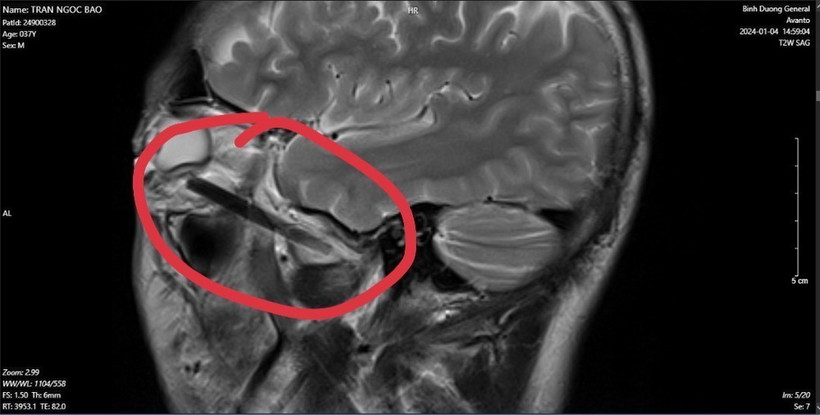

Hình ảnh dị vật trong mắt người đàn ông ở tỉnh Bình Dương. (Ảnh: TTXVN phát)

Các bác sỹ phát hiện một phần chiếc đũa dài khoảng 6cm, nằm sâu trong hốc mắt người đàn ông này.

Sau khi phẫu thật, các bác sỹ đã lấy được dị vật trong hốc mắt của người bệnh là đầu đũa gỗ bị gãy với chiều dài gần 6cm.

Theo các bác sỹ, dị vật hốc mắt là bệnh ít gặp, dị vật hốc mắt cần được lấy và điều trị kịp thời tránh viêm tổ chức hốc mắt và viêm thị thần kinh gây mất thị lực. May mắn đối với người bệnh là khi vào viện chỉ mới bị viêm tổ chức hốc mắt, chưa dẫn đến viêm thị thần kinh và được các bác sỹ chẩn đoán, điều trị kịp thời. Đây là một trường hợp mắc dị vật ở mắt phức tạp và khó xử lý vì dị vật nằm khá sâu, phẫu trường hẹp.